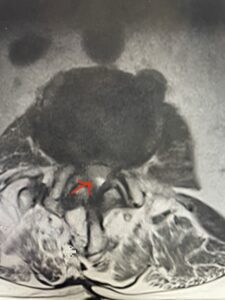

Fig 1a: Sagittal T2 weighted lumbar MRI demonstrating severe L2-3 stenosis (red arrow)

In patients who have lumbar spinal stenosis and significant cardio/pulmonary conditions, surgery is the last resort. However, some patients with these conditions may fail all means of conservative management where surgery becomes their only option for relief. In those patients, one should strive to do the least complex surgery that is necessary to get the job done for them. In this case study, we are confronted with a new problem in a 78 year-old male patient that was in poor medical condition who had had two prior lumbar laminectomies with resultant fusion and instrumentation from L4-S1. There was now retrolisthesis of L2-3 with severe stenosis (Fig.1)